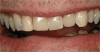

Figure  13   This patient was unhappy with the unesthetic appearance due to tooth surface loss.

Figure 13

Figure  14  Full-mouth rehabilitation with porcelain-fused-to-metal.

Figure 14